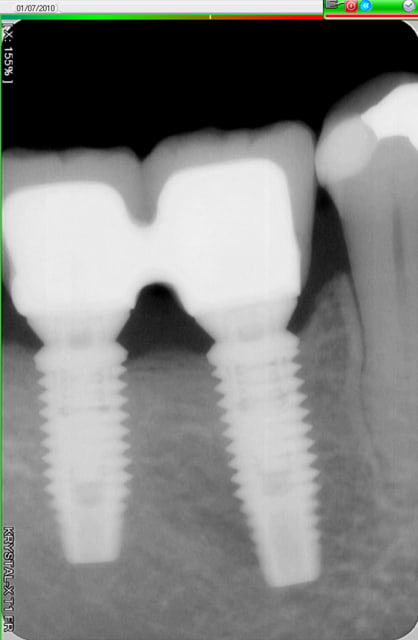

Voici trois Rx : cratère ou pas ? quel taux d'échec à 5 ans (tout les implants), ce sont les mêmes : 3I plateforme plate, deux temps chir, pas de plateform switching, pilier vissé prothèse scellée, 3 mois d'OI.

Crat 1 k8pnfh - Eugenol

Crat 2 ra8vyw - Eugenol

Crat 3 hpsffn - Eugenol